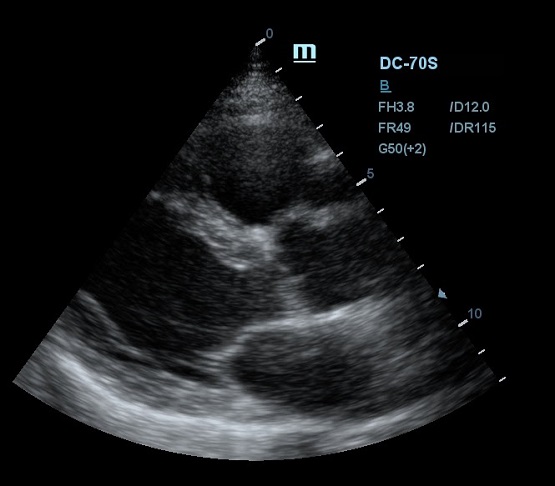

Благодаря постоянным инновациям, компания Mindray внедрила технологию iClear (адаптивная обработка изображений). Спекл - артефакт визуализации в виде акустического пятна - был препятствием для дифференциации структуры исследуемой ткани. iClear реализует агрессивное подавление спекл-паттернов, позволяя четко визуализировать анатомическую структуру на ультразвуковых изображениях. За счет уменьшения спекл-шума достигается лучшая дифференцировка тканей. Повышается контрастное разрешение без ущерба для пространственного разрешения. Уровень подавления спеклов можно выбрать под свои задачи, достаточно нажать кнопку или повернуть ручку, остальное сделает программный алгоритм.